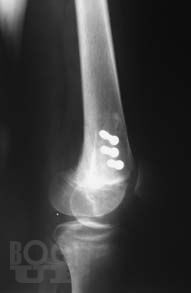

Книга посвящена сложному и разнообразному разделу травматологии – диагностике травматических повреждений крупных суставов у взрослых и детей. Приведены основные рентгеноанатомические сведения о суставах. Дана рентгенологическая характеристика разнообразных повреждений костей и мягких тканей, доступных рентгеновскому исследованию. Представлена рентгенологическая картина посттравматических, в том числе послеоперационных воспалительных осложнений – артритов.